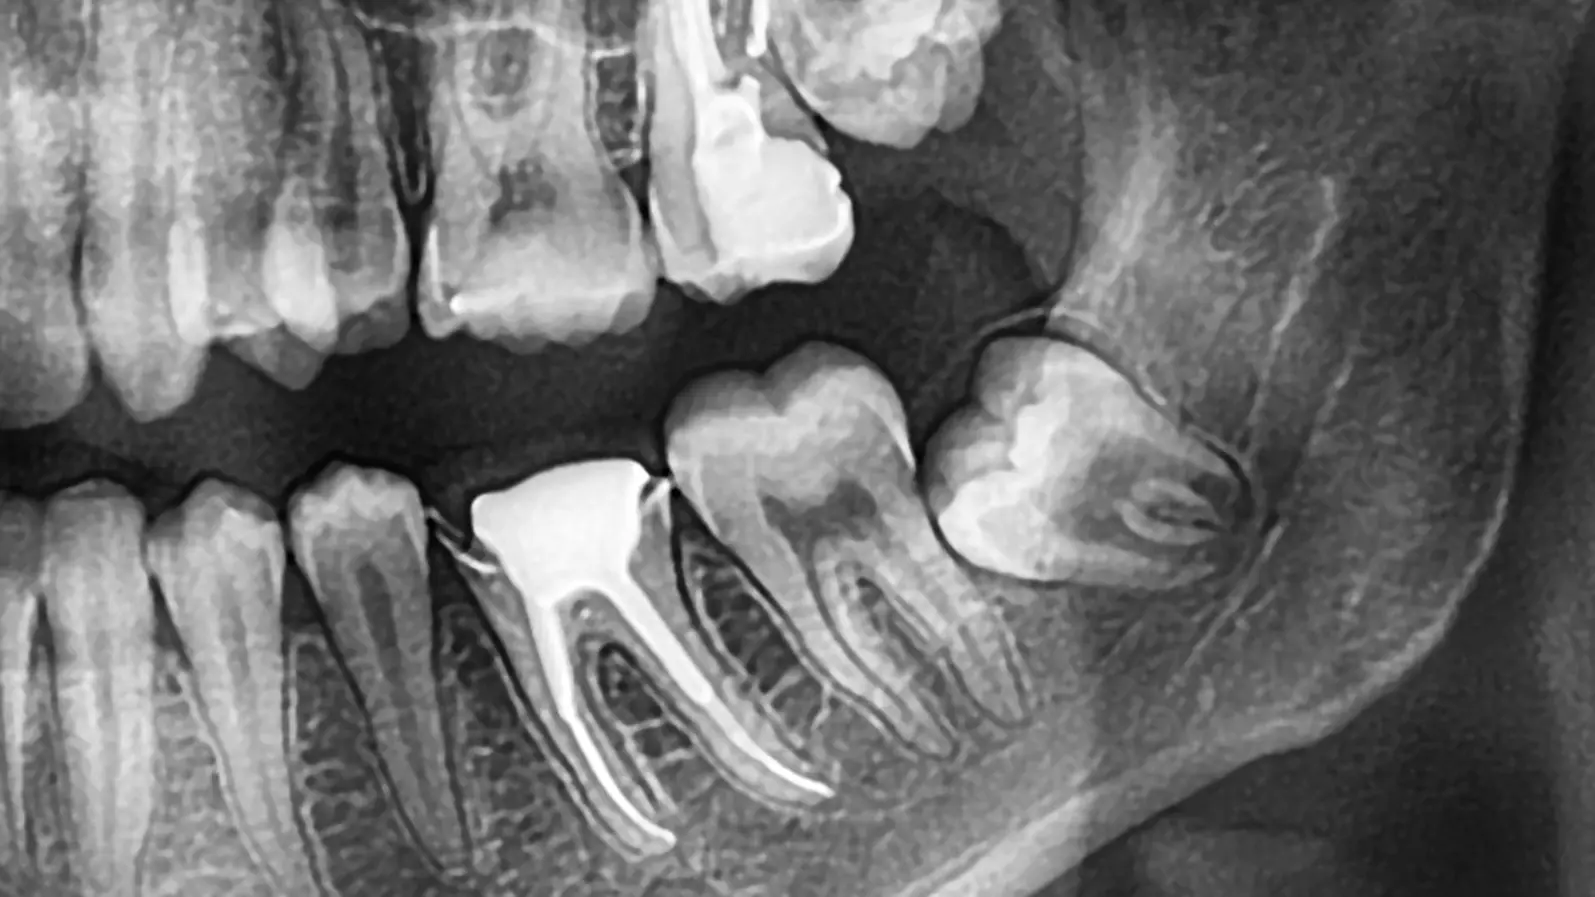

What a Panoramic X-ray Reveals About Quiet Third Molars in Young Adults

Have you ever wondered about those teeth tucked way in the back of your jaw? Your third molars, or wisdom teeth, are a common source of concern, often needing removal due to pain or infection like pericoronitis. However, many wisdom teeth remain silent, never causing trouble. A new study sheds light on how dental panoramic X-rays (PANs), the most frequent choice for third molar imaging , can help dentists identify these non-pathological, symptomless mandibular third molars.

The analysis revealed that mandibular third molars that were quiet and healthy shared several distinct features on the X-ray, which could be identified with 68–87% certainty.

The four most common characteristics of a symptomless, pericoronitis-free mandibular third molar were:

Deep in the Bone: Most reliably predicted by location, 87% of symptomless teeth were deep in the bone, at or below the cementoenamel junction (the point where the crown meets the root) of the second molar, or only just perforating the cortex (classes A, B, and C).

Mesioangular Inclination: 75% of these teeth were tilted forward (mesioangularly inclined).

Reduced Bone Level: 70% were associated with a reduced marginal bone level behind the second molar. Surprisingly, the greater the bone reduction, the fewer the symptoms, which the researchers suggest may be related to the ongoing eruption process and natural bone remodeling in this young age group, rather than pathology.

Incomplete Root Development: 68% had roots that were not fully formed (incomplete root development). This is often tied to the tooth still being unerupted.

In addition, 78% of these quiet teeth were clinically unerupted (not visible in the mouth). Interestingly, signs of pathological changes in the follicle (the sac around the crown) were not a reliable predictor of a tooth's clinical status.